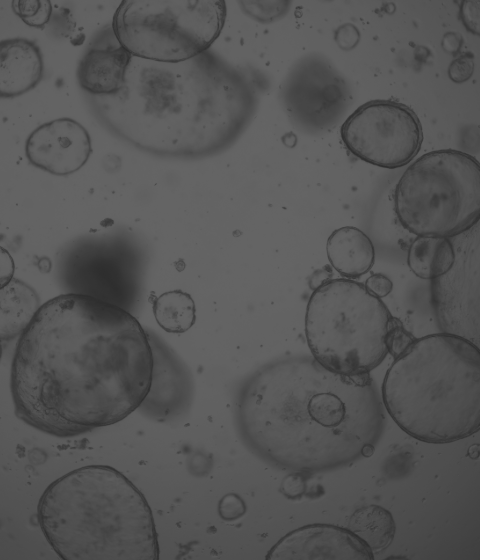

廈門模基生物科技有限公司致力于3D細(xì)胞培養(yǎng)核心原材料的研發(fā)與產(chǎn)業(yè)化升級,是國內(nèi)一家從科研做起,從實驗研究中一路走來的全流程自主研發(fā)、自主生產(chǎn)的企業(yè)。目前公司的產(chǎn)品有基質(zhì)膠、類器官培養(yǎng)基、細(xì)胞因子、3D細(xì)胞培養(yǎng)耗材、3D細(xì)胞培養(yǎng)智能顯微鏡等。公司擁有4大技術(shù)研發(fā)中心:分子克隆和細(xì)胞編輯中心、實驗動物中心、蛋白表達和純化平臺、類器官質(zhì)檢系統(tǒng)和自動化。